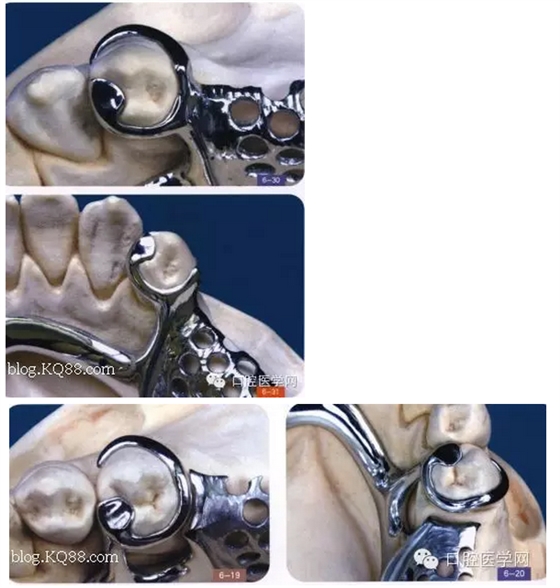

其實RPI,RPA卡換組對于后牙游離缺失在臨床中很常用,CPI卡換組由三部分組成,近中和支托,遠中臨面板,和頰側(cè)I桿組成,近中和支托起一個應(yīng)力中斷作用,能有效預(yù)防近中基牙扭轉(zhuǎn)

1是近中合支托,2是臨面板,3是I桿

CPI卡環(huán)應(yīng)用于遠中游離缺失,近中基牙不健康的基牙,當遠中產(chǎn)生一個向黏膜處的壓力時,把力量通過近中和支托,傳寄給基牙,而不是直接在遠中處直接傳給給基牙,這樣就產(chǎn)生了一個應(yīng)力中斷作用能有效保護基牙,同時頰側(cè)和遠中的I桿和臨面板下沉,滑動,能有效預(yù)防基牙扭轉(zhuǎn),同時I型卡環(huán)與基牙的接觸面積比較小能防止食物存留預(yù)防繼發(fā)齲但是有一前提:游離缺失處,牙槽脊條件比較好,對于牙槽脊條件差者,要設(shè)計遠中合支托,如果頰側(cè)牙體倒凹大,口腔前庭小于5mm者要設(shè)計CPA卡換組(以下圖片來自中醫(yī)大)

(CPA及變異CPA卡環(huán)組)